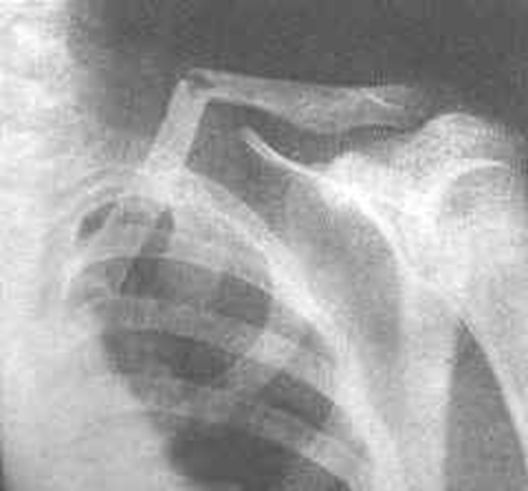

锁骨骨折

常发生在中段。多为横断或斜行骨折,内侧断端受胸锁乳突肌的牵拉常向上后移位,外侧端受上肢的重力作用向内、下移位,形成凸面向上的成角、错位缩短畸形。